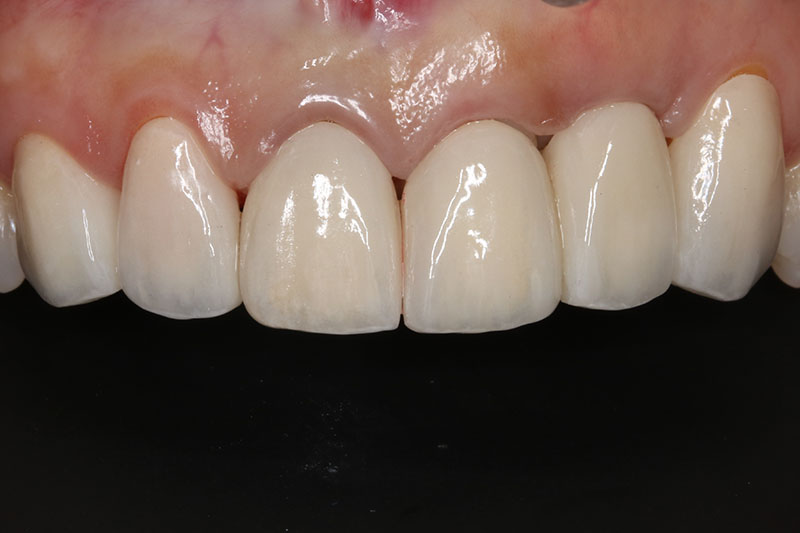

缺牙多顆

案例一

術後